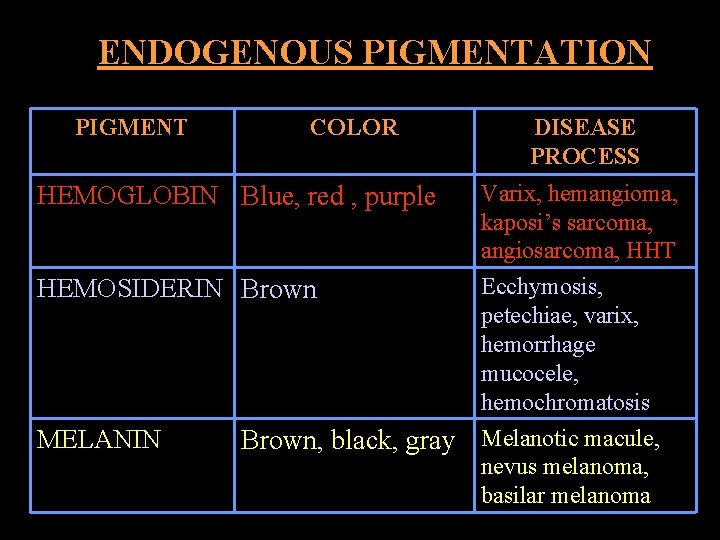

ENDOGENOUS PIGMENTATION PIGMENT COLOR DISEASE PROCESS HEMOGLOBIN Blue, red , purple Varix, hemangioma, kaposi’s sarcoma, angiosarcoma, HHT HEMOSIDERIN Brown Ecchymosis, petechiae, varix, hemorrhage mucocele, hemochromatosis Melanotic macule, nevus melanoma, basilar melanoma MELANIN Brown, black, gray